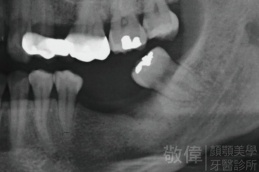

治療前-全口X光   治療後-全口X光